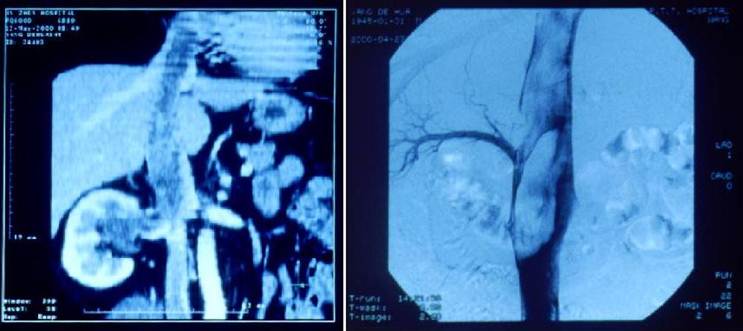

Computerized tomography (CT) scan and magnetic resonance imaging (MRI) revealed a mass in the right kidney with extension into the right renal vein and inferior vena cava, and further extension into the right atrium (Fig. 1A). Retrograde urography confirmed that the right renal pelvis was compressed and distorted, but was unobstructed. The right ureter also was unobstructed. Digital subtraction angiography revealed tumor thrombus in the inferior vena cava extending from the level of the right renal vein to the right atrium (Figs 1B). Laboratory investigations revealed no abnormalities. Renal function tests were normal. Urine analysis revealed no microscopic hematuria.

Figure 1

Multi-plana Reconstruction of CT scan before operation showing a mass in the right renal area and propagation through the inferior vena cava into the right atrium 1A (left). Digital subtraction angiography performed before surgery showing huge tumoral thrombus in the inferior vena cava extension upward from over the right renal vein level 1B (right).